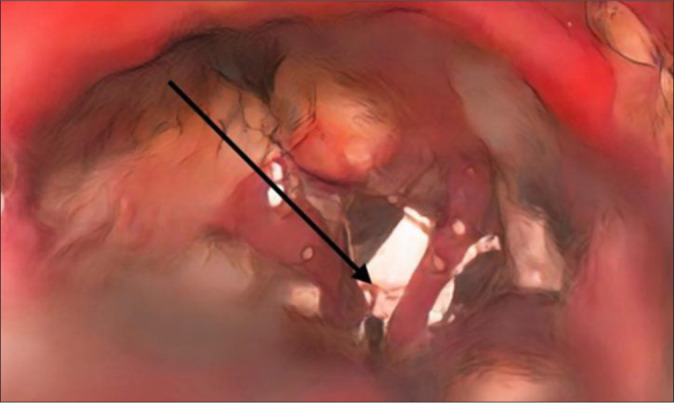

Case description: We report a case of a 40-year-old female suffering from debilitating right-sided facial pain due to a rare "scissor effect" produced by the superior petrosal sinus and Dandy's vein (vein of the cerebellomesencephalic fissure) compressing the trigeminal nerve. Surgical decompression was performed by interposing autologous skeletal muscle wrapped with Surgicel between the conflicting venous structures and the nerve. The patient achieved complete pain relief without neurological deficits.